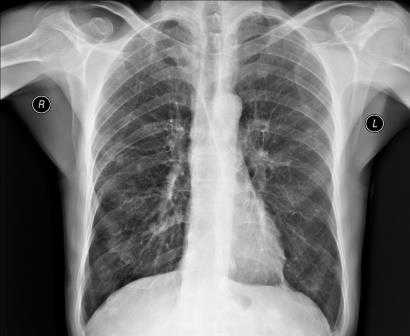

Снимки обычно делаются в заднепередней и левой боковой проекциях. В заднепередней проекции благодаря уменьшению расстояния между сердцем и рентгеновской пленкой изображение сердца получается более четким и менее искаженным, чем в переднезадней. У лежачего пациента можно воспользоваться передвижным рентгеновским аппаратом, но он позволяет делать снимки только в переднезадней проекции.

Нормальная картина

В норме на снимках, выполненных в заднепередней проекции, ширина грудной клетки по меньшей мере в 2 раза превышает поперечный размер сердца. В то же время в переднезадней проекции относительные размеры и положение сердца могут быть другими; возможно усиление тени сердца и дуги аорты. Когда исследование проводится с контрольной целью, рентгенограммы грудной клетки должны подтверждать правильное положение катетеров и водителей ритма.

Отклонение от нормы

Изменение формы сердца обычно заключается в увеличении левого или правого желудочка, левого предсердия или даже нескольких полостей. При увеличении левого желудочка в заднепередней проекции левая граница сердца становится круглой и выпуклой с боковым расширением в своей нижней части, а в боковой проекции определяется выбухание левого желудочка кзади. При увеличении правого желудочка в заднепередней проекции наблюдается вторичное изменение левой границы сердца за счет расширения тени легочной артерии, а в боковой - расширение тени выносящего тракта правого желудочка. При увеличении левого предсердия его плотность на рентгенограмме в заднепередней проекции увеличивается вдвое, левая граница сердца сглаживается, левый главный бронх смещается кверху. В редких случаях правая граница сердца над проекцией правого желудочка расширяется кнаружи. В боковой проекции определяется выбухание левого предсердия кзади. Начальными признаками застоя в малом круге кровообращения на снимках, сделанных в заднепередней проекции, являются расширение тени легочных вен в верхнебоковой части корней легких и сосудистые тени, расположенные горизонтально вдоль нижней части правой границы сердца. Хроническая легочная венозная гипертензия приводит к формированию рисунка по типу оленьих рогов (из расширенных верхних и нормальных или суженных нижних легочных вен). При остром отеке легких увеличение плотности в центре легочных полей может по форме напоминать бабочку. Интерстициальный отек легких может напоминать снежные хлопья на фоне легочных полей.